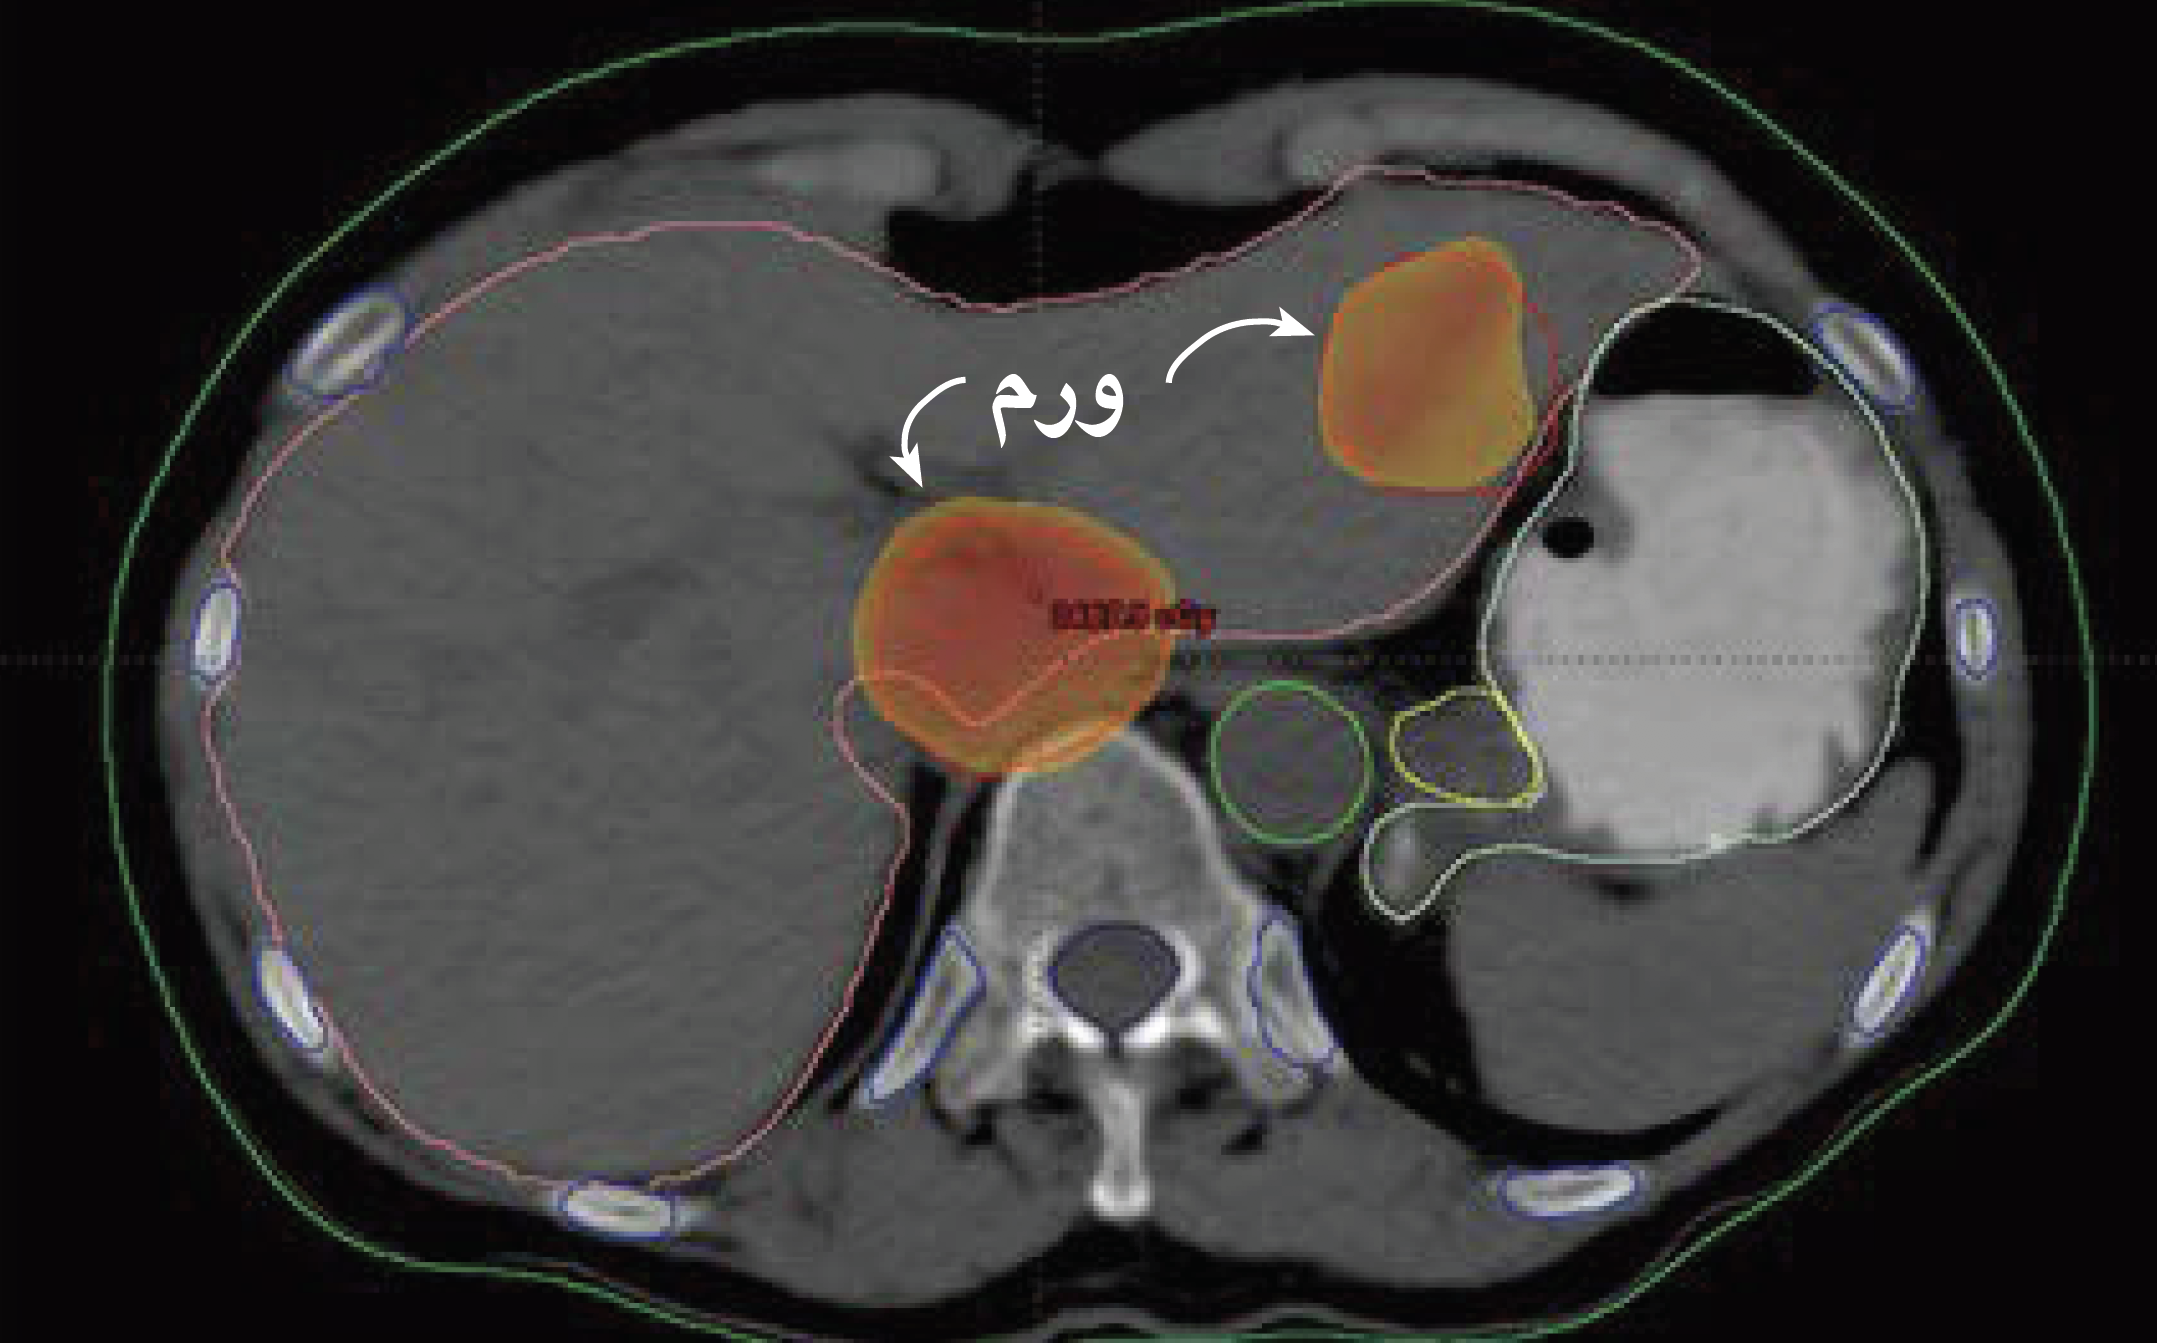

???? ????? ??? ???? ?????? ?????????? ?????? ??????? ?? ?????? ???????? ????? ???? ?????? ???????? ?????? ??????? (?????? ??: ?????? ?????? ???????? ???)

??????? ????? ????? ????? ?? ?????? ?????? ???????? ?????? ?? ???? ??? ???????? ? ?????? ???????? ?????? ??????? ????? ????? ????? ?????? ?????? ????? ?????? ???????? ????? ??? ?? ????? ????? ???? ?????? ??????? ??????? (HCC)? ??? ??????? ?????? ?????? ??? ?????? ?? ???.